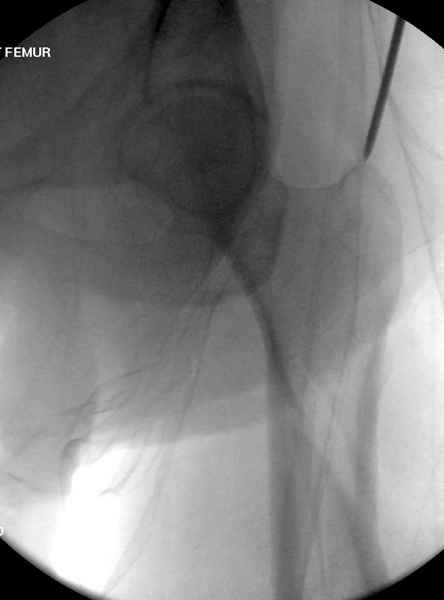

Среди русскоговорящих коллег Ортофорум стал одним из мест, где многие из нас черпают знания для решения своих ежедневных проблем в виде практических советов и обмена опытом. Кроме таких советов, Ортофорум стал источником новых познаний среди ортопедов, особенно по редко встречающимся состояниям в ортопедии. Продолжая традицию, я хотел бы представить редко встречающий случай перелома бедра у больного с гемофилией. Больному 42, гемофилия типа А, из истории упал с высоты около 1,5 метра, переправлен из другой больницы. По происхождению мексиканец, 10 лет назад по поводу артроза пр. коленного сустава в Мексике сделано протезирование, которое закончилось ампутацией выше коленного сустава. При поступлении бедро напряженное, сосудистых и неврологических расстройств нет. На рентгенограмме оскольчатый перелом бедра с вовлечением проксимальной спирали в шейку бедра. Хотели бы знать тактику ведения подобных больных и на что надо обратить внимание? Djoldas Kuldjanov, MD Department of Orthopedic Surgery St. Louis University Medical Center

Учитывая, что случай ургентный, больной поступил вечером, не стали делать вытяжение и срочно провели операцию по фиксации перелома бедра антеградным штифтом Versa Nail от DePuy.

Для профилактики дальнейшего раскола в шейке предварительно во время проксимального рассверливания спереди и сзади провели временные спицы, которые в дальнейшем были заменены на шурупы (miss nail method)